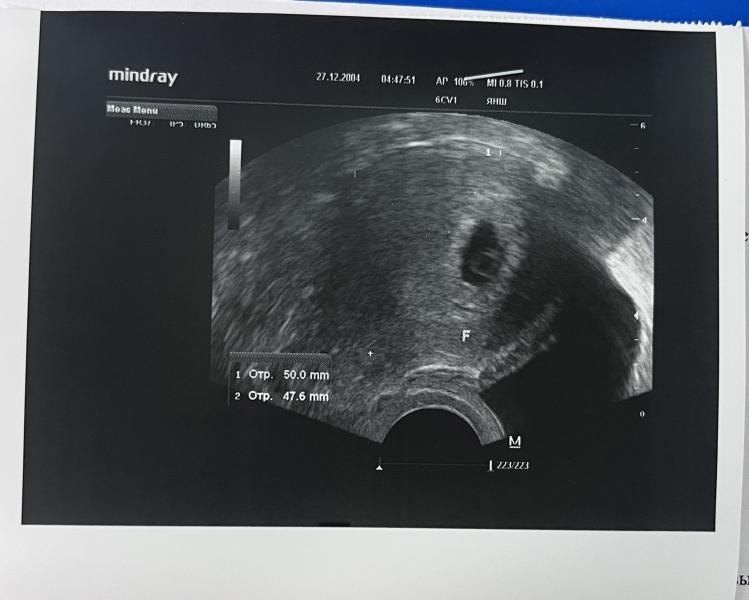

УЗИ на 23 дпп: сердцебиение есть! Все хорошо, отличные результаты после обследования?

Сходили на УЗИ, все супер

Сегодня 23дпп, сердцебиение прослушивается ✨🙏🏻

Репродуктолог сказала, что именно прослушивается)